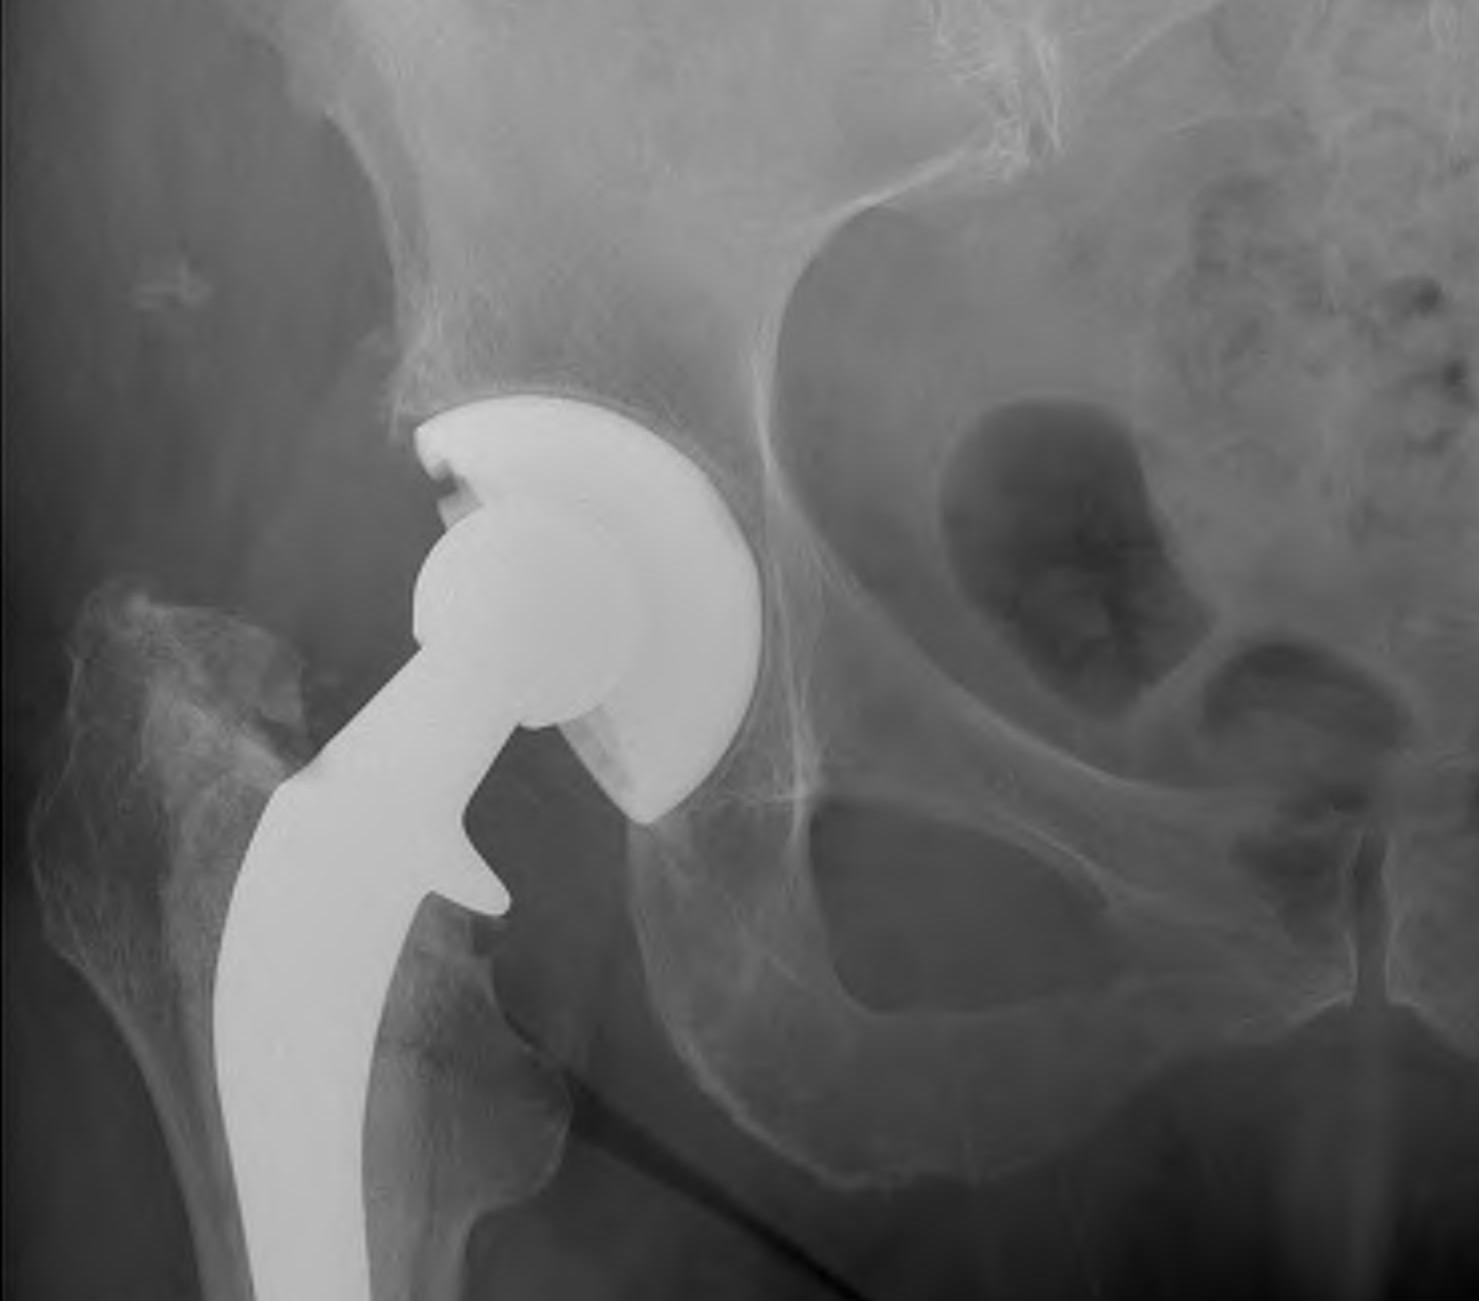

Joint replacement surgery is recommended when severe joint damage causes persistent pain, stiffness, or loss of mobility that interferes with everyday life. Revision surgery is required when a previous joint replacement no longer functions properly due to wear, loosening, infection, or implant failure. With modern surgical techniques and improved implant designs, both procedures can deliver long-lasting pain relief and restored joint function.

Treatment Options for Joint Replacement & Revision

-> Hip replacement ->Knee replacement ->Shoulder replacement ->Advanced implant techniques